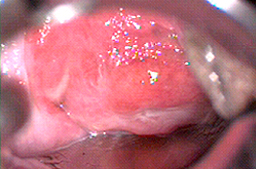

El mejor aparato actualmente que nos permite medir y regular con precisión la profundidad de la piel que se desea destruir o la piel infectada es el LASER CO2, cuando es utilizado por un colposcopista experto,(el cual se adquiere cuando un ginecólogo realiza el entrenamiento en colposcopía por seis meses en una Clínica de Displasias), y capacitación técnica en el manejo del laser CO2. Ya que los tratamientos deben tener una profundidad menor a 1 mm (800 micras máximo) para que no afecten las terminaciones nerviosas y por lo tanto no dejen secuelas. Su aplicación se hace bajo anestesia local por lo que es indolora. Su tasa de éxito es alta, del 89% con recaídas del 8% durante los primeros 2 años. Por lo que actualmente es el mejor tratamiento para el Virus del Papiloma Humano y las lesiones precancerosas de genitales externos, vagina y las lesiones extensas en cérvix, (extensión de lesiones a fondos de saco vaginales). Aclarando que la tasa de éxito depende de la capacitación del médico que lo aplica, existen estudios en que la tasa de éxito es incluso del 50% debido a la mala técnica utilizada.